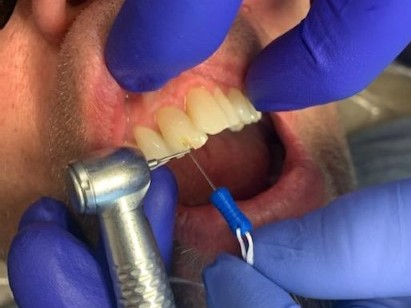

2

Anterior broken tooth. Double DentXpinTM repair.